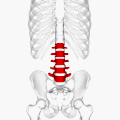

Position of human lumbar vertebrae (shown in red). It consists of 5 bones, from the top down, L1, L2, L3, L4 and L5.

In human anatomy, the five vertebrae are between the rib cage and the pelvis. They are the largest segments of the vertebral column and are characterized by the absence of the foramen transversarium within the transverse process (since it is only found in the cervical region) and by the absence of facets on the sides of the body (as found only in the thoracic region). They are designated L1 to L5, starting at the top. The lumbar vertebrae help support the weight of the body, and permit movement.